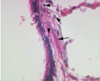

What is this showing in the lungs and why?

Pulmonary TB

Early Mycobacterium tuberculosus - early caseous granuloma , central area of caseous necrosis (CN), surrounded by macrophages (M) which fuse to giant Langerhans cells (L). Arrows = rim of lymphocytes.